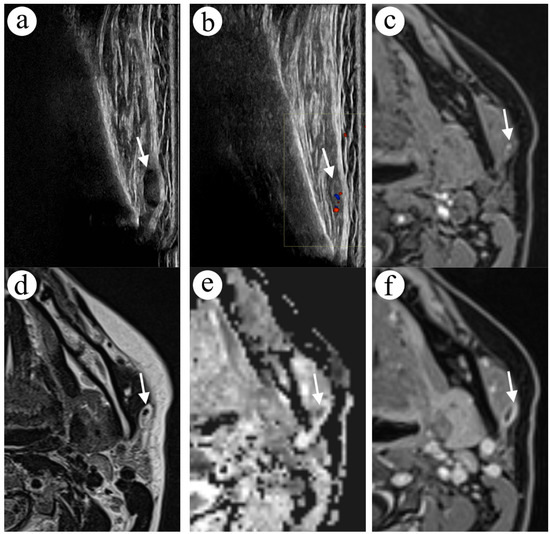

2.1. Case 1